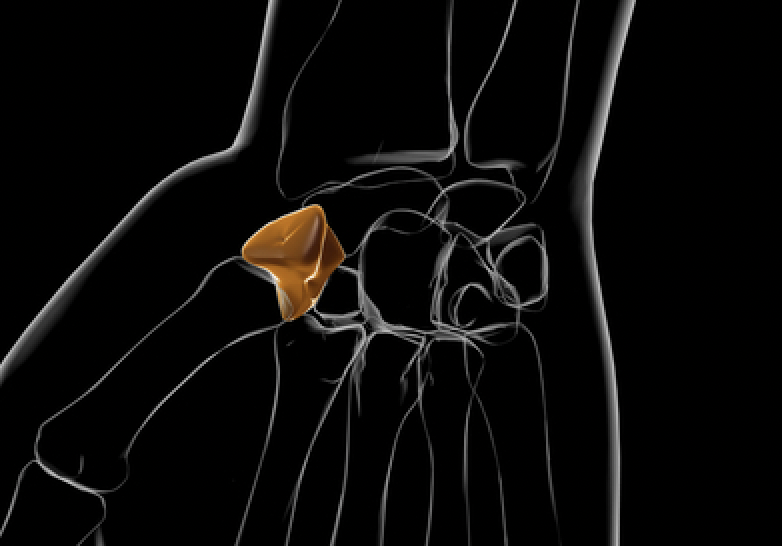

对于舟骨骨折,我们是否还应该固定拇指,还是只固定腕部石膏就同样有效?

文章:Harper, KJ、Rees, Y.、Tan, NX、Li, H.、Fonseca, EA、Quach, PG、Lee, GS、Brayshaw, JR 和 McGarry, S. (2025)。 ...